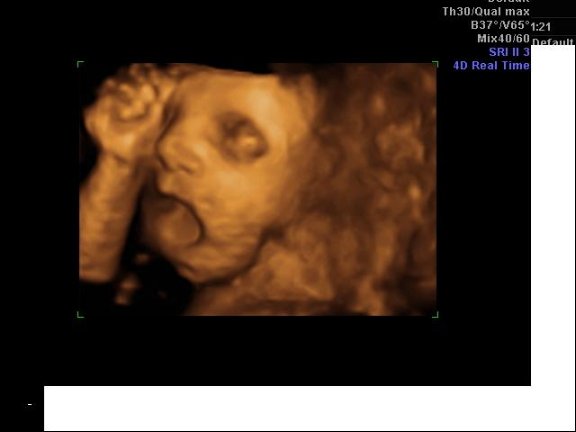

Rakok 4D képet Milánról.Nagyon jó volt csak iszonyat álmos volt a ksfiam.Egyfolytában ásítozott: Kép Kép